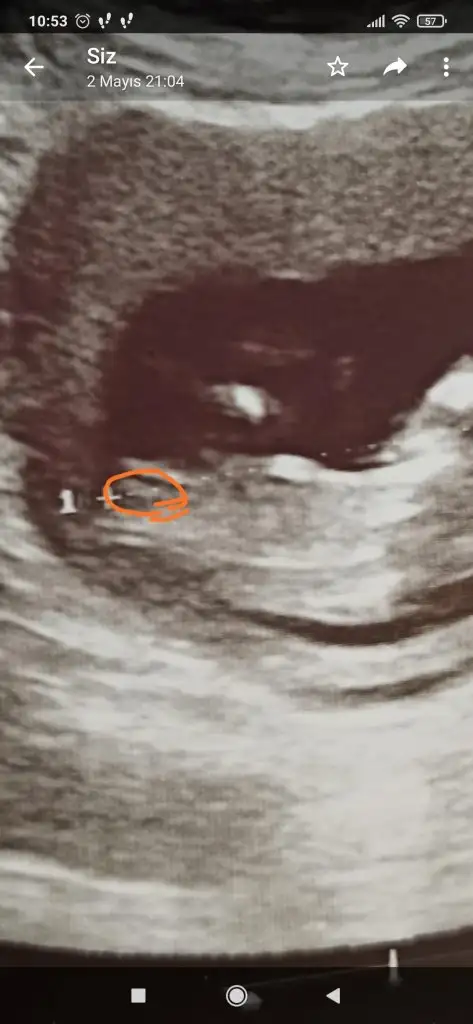

Canım 6 7 haftalıkken karından sol taraftaydi şimdi 12+3 ve 13+6 yi atacağım 12+3 deki çıkıntı düz bakıyor nub teorisi diyoruz buna ordan kız olduğunu anlamıştım

• Screenshot_2021-05-12-10-53-09-404_com.whatsapp.webp

Screenshot_2021-05-12-10-53-09-404_com.whatsapp.webp

20,7 KB · Görüntüleme: 108